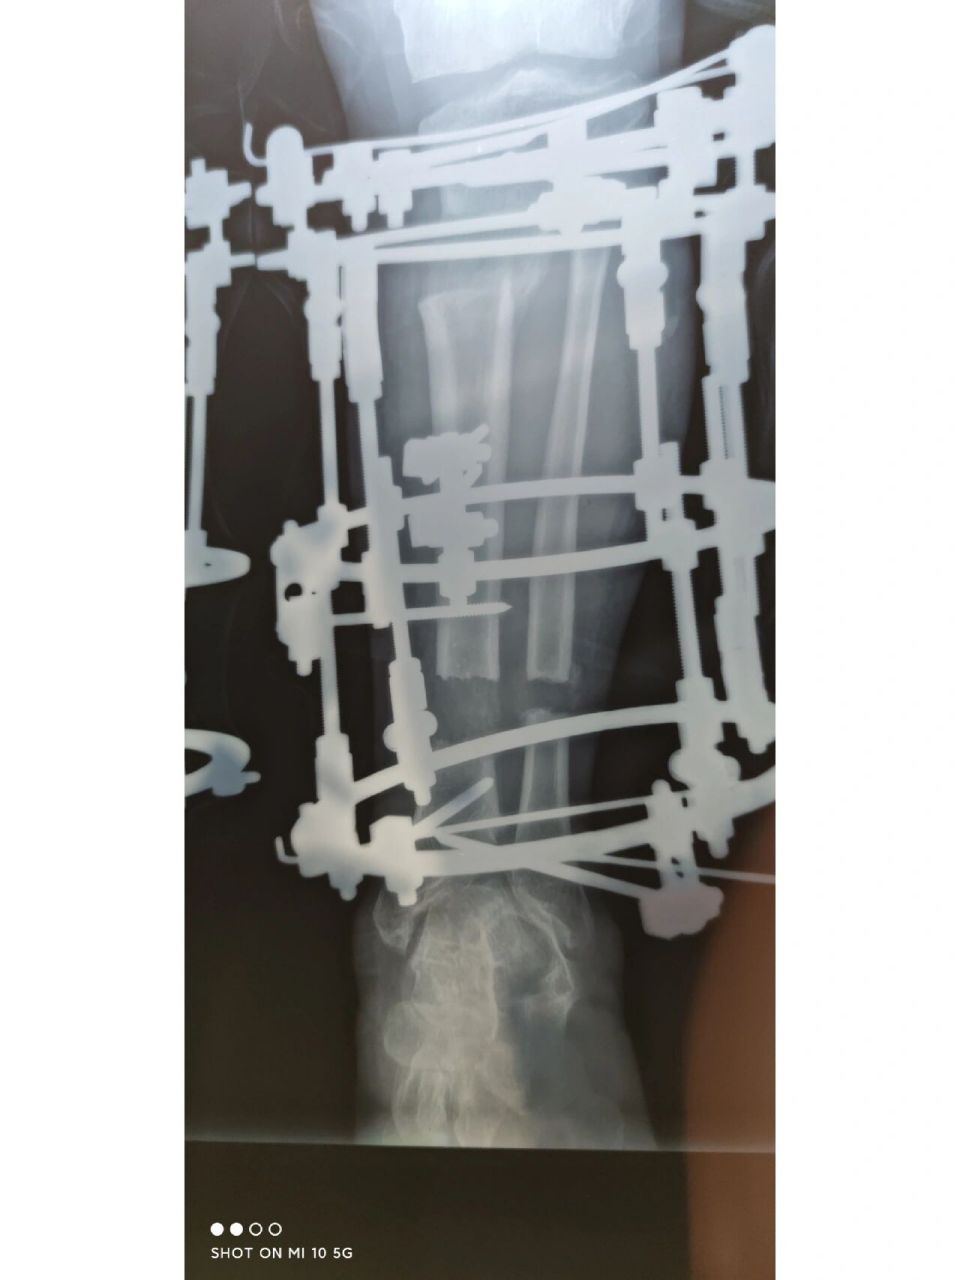

踝骨骨折,全断裂,新型影像清晰一目了然.#医学影像 - 抖音

图片尺寸1440x1920